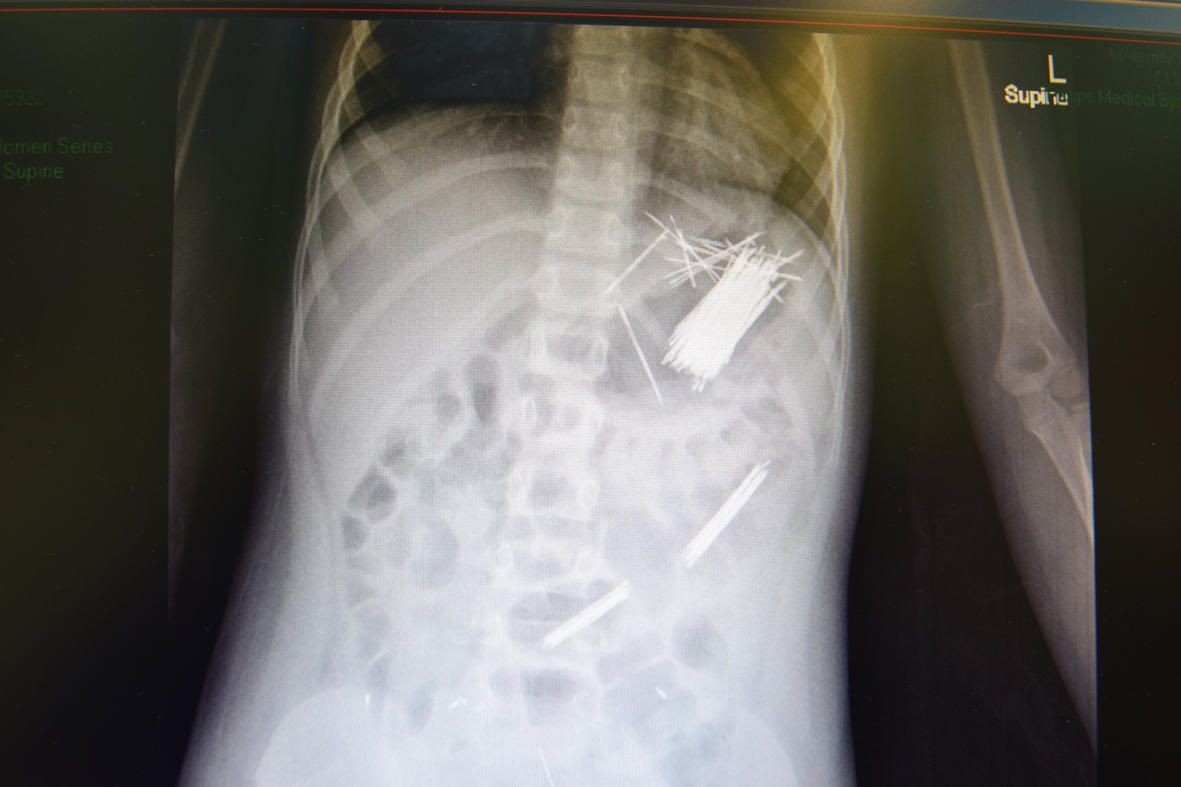

المواطن – سعيد ال هطلاء – عسير

تمكن فريق طبي بمستشفى أبها للولادة والأطفال بقيادة الدكتور عادل محي الدين الشهراني من استخراج عدد (50) بنسة شعر من معدة طفل يبلغ من العمر سبع سنوات، وذلك عن طريق جراحة المنظار وقد استغرقت العملية ثلاث ساعات، وتم نقل المريض لجناح التنويم بعد أجراء العملية بدون أي مضاعفات.

وأوضح المتحدث الرسمي لصحة المنطقة سعيد بن عبد الله النقير أنه منذ افتتاح قسم مناظير الجهاز الهضمي بالمستشفى تم إجراء 130 عملية تنوعت بين استقبال أجسام غريبة ونزيف الدوالي والنزيف الشرجي.

ومن جهته قال مدير مستشفى أبها للولادة والأطفال الدكتور علي بن مستور القحطاني: إن هذه العملية تضاف إلي سجل إنجازات أطباء المستشفى، مشيرًا إلى أن المستشفى مرجعي لاستقبال حالات الولادة والأطفال على مستوى المنطقة.

وأهاب القحطاني بجميع أولياء الأمور بمتابعة أبنائهم أثناء اللعب وعدم تركهم يلهون بعيدًا عن رقابة الأسرة للمحافظة على سلامتهم وتجنبهم مصادر الخطر.